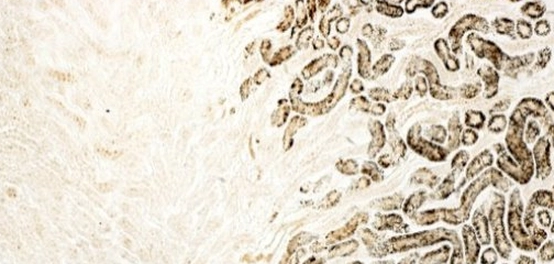

تُعرف الليسوسومات (Lysosome) بأنها عضيات خلوية أساسية موجودة في معظم الخلايا حقيقية النواة. تُشبه هذه العضيات “الجهاز الهضمي” للخلية، حيث تلعب دوراً حيوياً في هضم الجزيئات الكبيرة، وأجزاء الخلايا التالفة، والكائنات الدقيقة الغازية. تتشكل الليسوسومات عن طريق التبرعم من جهاز غولجي، وتختلف أحجامها وأشكالها و أعدادها من خلية لأخرى. وتحيط بها غشاء واحد يحمي باقي الخلية من أنزيماتها القوية.

تنتشر الليسوسومات في جميع الخلايا الحيوانية، وتكون أكثر وفرة في الخلايا التي تتميز بنشاط بلعمي عالٍ، مثل خلايا الدم البيضاء والخلايا الأكولة.

تُعتبر الجسيمات الأولية المرحلة الأولى في تكوين الليسوسومات، حيث تنشأ من جهاز غولجي والشبكة الإندوبلازمية الخشنة. تظهر على شكل حويصلات صغيرة محاطة بغشاء فوسفوري واحد، وتحتوي على إنزيمات هضمية تُعرف بالهيدرولازات الحمضية. يُعد الوسط الحمضي (الرقم الهيدروجيني حوالي 5) ضروريًا لتنشيط هذه الإنزيمات.

عندما تندمج الجسيمات الأولية مع جسيمات بلعمية (خلال عملية البلعمة، التي تُدخِل مواداً من خارج الخلية إلى داخلها)، يحدث الهضم داخل الحويصلات الناتجة، مما يؤدي إلى تكوين أنواع أخرى من الليسوسومات.

تنتج الجسيمات الحالة الثانوية من اندماج الجسيمات الأولية مع جسيمات بلعمية محملة بالمواد التي تم ابتلاعها من خارج الخلية. هذا الاندماج يُنشط الإنزيمات الهضمية، مما يسمح لها بهضم الجزيئات الحيوية المختلفة، مثل الأحماض النووية والدهون. توجد هذه الجسيمات في العديد من أنواع الخلايا، بما في ذلك خلايا الدم وخلايا الأنسجة.